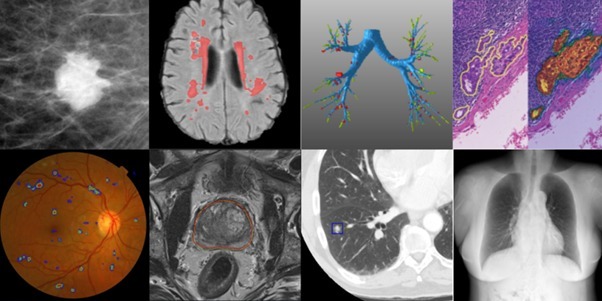

Our Solution will help the medical staff’s in such a way that in any of the critical condition, if doctors are not available to tackle few patient as due to emergency, so other medical supervisors can too use it as for primary detection and then consult to higher medical staff. I am solving the following diseases:-

- Diabetic Retinopathy (71.36%)

- Breast Cancer Detection (100%)

- Chronic Kidney Diseases Detection (100%)

- COVID phenomenon detection (95.45%)

- Parkinson Spiral through detection (50%)

- Heart Diseases Prediction (80.32%)

- Brain Tumor Detection ( working over the approach)

As modern problem need modern solution, so for this problem we are providing a AI based diseases diagnostic system (DDS) which is a software that will detect the diseases. Our Solution will help the medical staff ’s in such a way that in any of the critical condition, if doctors are not available to tackle few patient as due to emergency, so other medical supervisors can too use it as for primary detection and then consult to higher medical